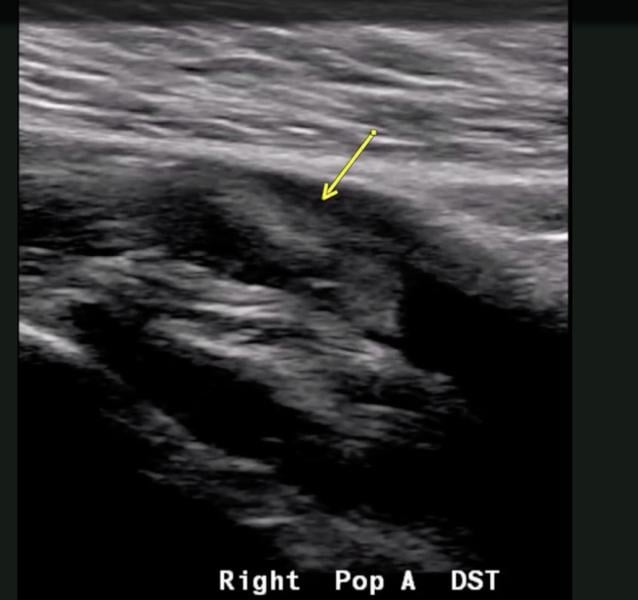

This photo gallery shows the variety of radiological presentations of COVID-19 (SARS-CoV-2) in medical imaging, including computed tomography (CT), radiograph X-rays, ultrasound, echocardiograms and magnetic resonance imaging (MRI). The radiology images show examples of typical COVID pneumonia in the lungs and the numerous complications the virus causes in the body in multiple organs, including the brain, kidneys, heart, abdomen and vascular system.

Ultrasound, especially hand-held ultrasound imaging devices, have become a primary imaging modality for novel coronavirus because of the ease to bag the device and sterilize it after use. CT and mobile X-ray systems are also used as front-line imaging systems for COVID-positive or suspected COVID patients.